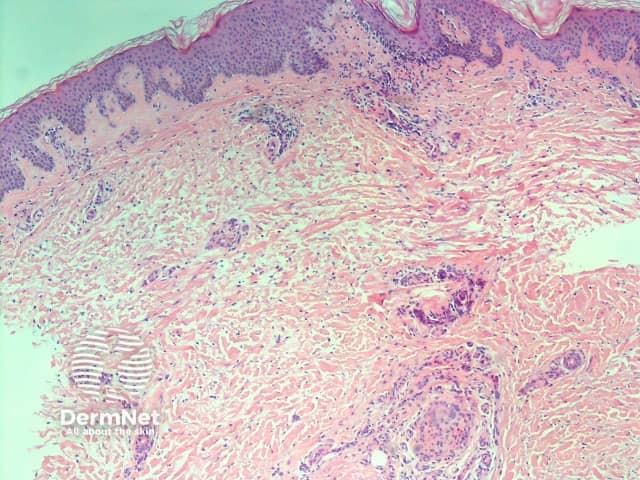

If a biopsy is done, histopathology typically shows deposition of mucin (glycosaminoglycans) throughout the dermis and subcutis.

H&E stain

Deposited mucin promotes dermal oedema by promoting the retention of fluid in the skin. This results in compression/occlusion of small peripheral lymphatics and lymphoedema.

The biopsy also shows attenuation of collagen fibres; they may be frayed, fragmented and widely separated. Stellate (star-shaped) fibroblasts are often observed, but the number of fibroblasts remains normal. Often a mild, superficial lymphocytic infiltrate around blood vessels is seen, and the overlying epidermis may show hyperkeratosis (increased scale).